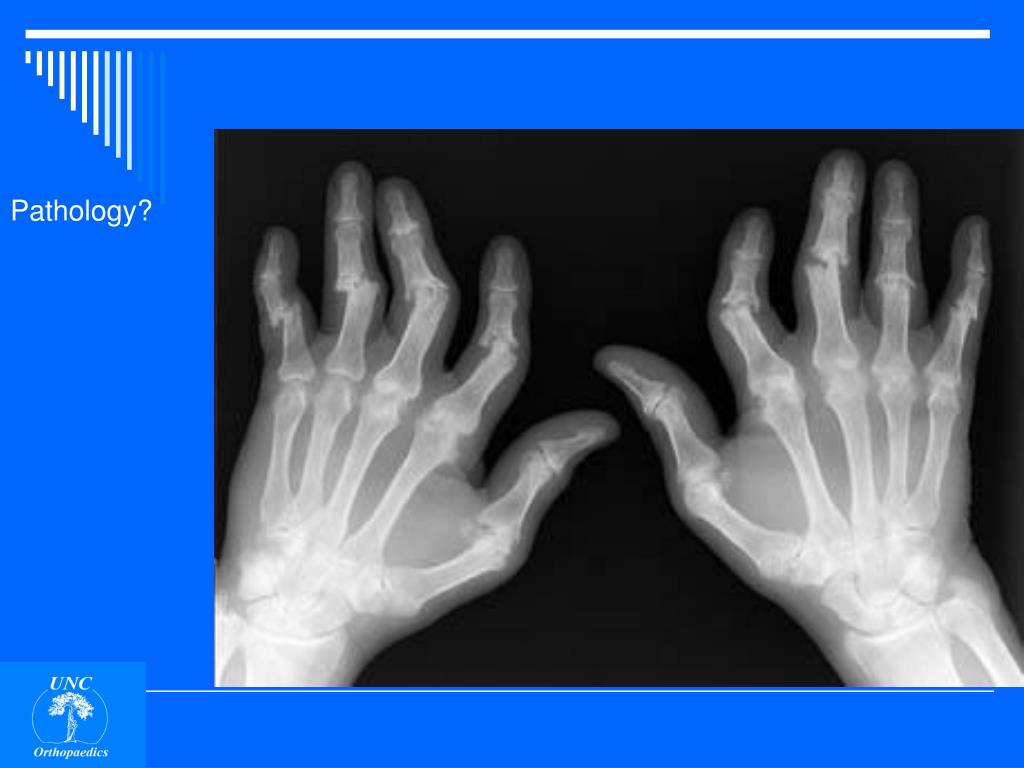

12. Pathology?

13. Pathology? Destructive erosions IP and MP joints Pencil in cup” deformities

14. Pathology? Destructive erosions IP and MP joints Pencil in cup” deformities Psoriatic arthritis

15. Pathology?